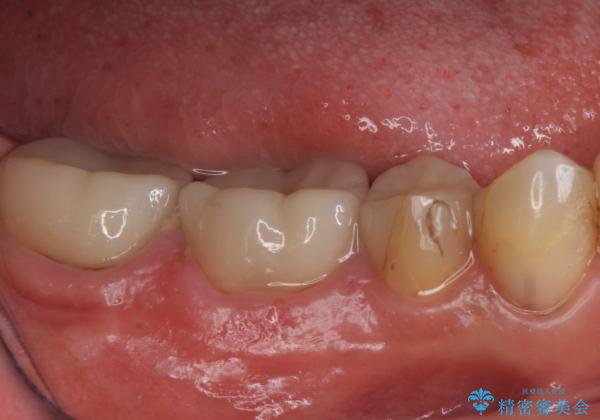

樹脂で継ぎ接ぎになった歯 セラミッククラウンでの治療

- 樹脂の材料の着色が気になるとのことで来院されました。

継ぎ接ぎになっている部分が多かったためクラウンでの治療となりました。

樹脂の材料と歯の境界部分は虫歯・着色の好発部位となります。

度重なる治療で継ぎ接ぎになってしまった場合はクラウンで歯を覆った方が虫歯・着色のリスクを減らすことができます。